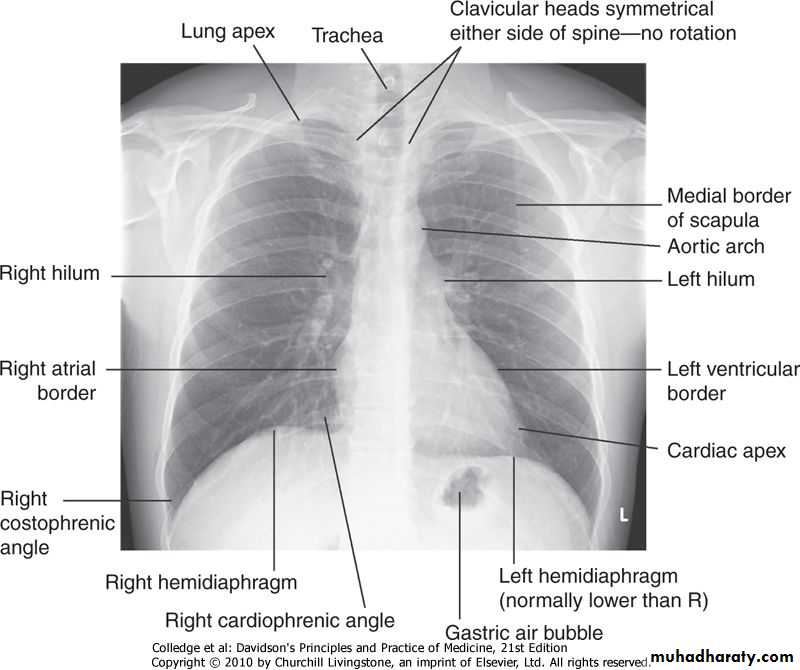

Imaging The 'plain' chest X-ray

This is performed on the majority of patients suspected of having chest disease.A postero-anterior (PA) film provides information on the lung fields, heart, mediastinum, vascular structures and the thoracic cage .

Additional information may be obtained from a lateral film, particularly if pathology is suspected behind the heart shadow or deep in the diaphragmatic